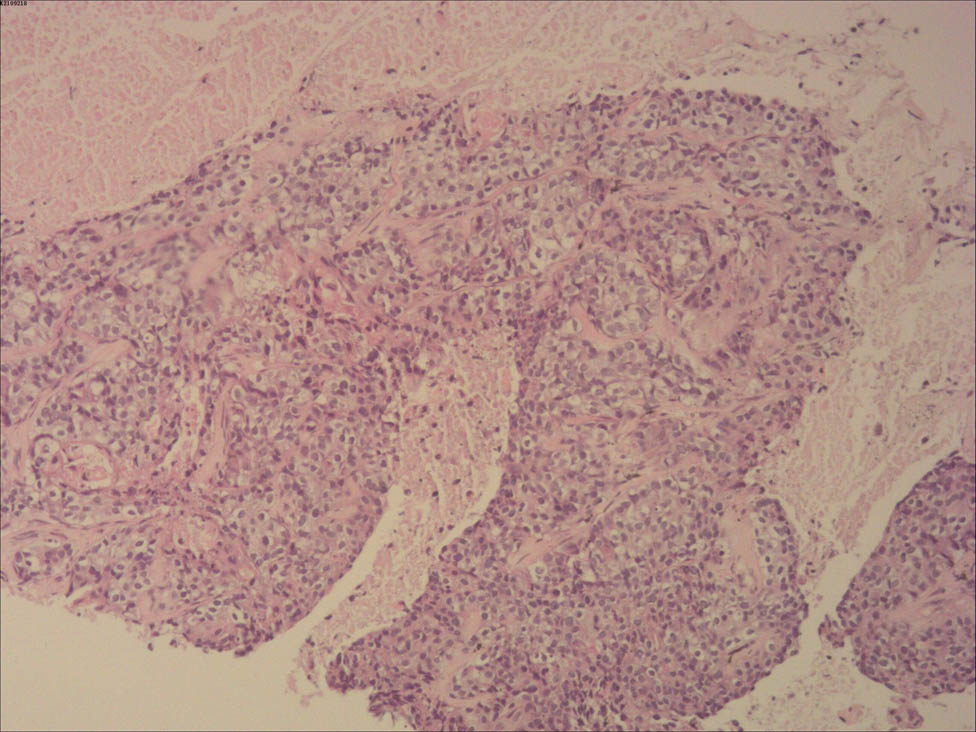

The patient had received six cycles of TEC chemotherapy (docetaxel, 700 mg; epirubicin, 100 mg; cyclophosphamide 500 mg; 21 days), initiated after the modified radical mastectomy, and radiotherapy (RT) at a dosage of 48 Gy/25 f/5 days a week to treat the lymph node of the right superior and inferior clavicular fossa and right chest for 5 weeks. The follow-up investigations were advised every 6 months including breast, abdomen and lymph node US, blood routine, liver and kidney function, and tumor markers and chest CT every year. However, she did not perform any checking items for 18 months since RT. Twenty-four months later after surgery, she was admitted again for dyspnea and chest discomfort; chest CT (Figure 3) revealed that there were probable metastatic lesions in lungs (maximum: 29 mm × 27 mm), liver (maximum: 12 mm × 10 mm), and mediastinal lymph nodes (maximum: 26 mm), with pleural effusion in the right thoracic cavity. The lung nodule was diagnosed as metastasis from breast invasive carcinoma by CT guided needle biopsy (Figure 4). Immunohistochemical analysis revealed that cells were ER, PR, PF-L1, SOX10, Napsin A, thyroid transcription factor-1, GCDFP-15 negative, HER-2 (2+) but in situ hybridization negative, CK-P and GATA-3 positive, proliferative index with KI-67 was 40%, and BRCA1 was local positive. The patient refused further treatment and died 3 months later. The related indicators of tests and examinations throughout the patient are presented in Table 1.

Histopathology of lung nodule (10×). This picture showed that lung nodule was metastasized from breast invasive carcinoma.